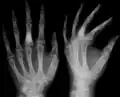

| X-ray image showing enchondromas localized in the lower part of the radius of a 7-year-old girl with Ollier disease. | |

Abnormal bone growth such as shortening or thickening and deformity may be observed in patients of Ollier disease. These bone lesions are visible at birth using radiography but are usually not screened or examined for until clinical manifestations present during early childhood. However, some patients may exhibit no signs of any symptoms.[1] One study found thirteen to be the mean age of diagnosis in patients with Ollier disease. In an X-ray, there would normally be the presence of several homogeneous lesions of an oval or elongated shape with bone edges that are slightly thickened.[3] With age, these lesions may calcify and appear as diffusely minute spots or stippled. Fan-like septations or streaks would be indicative of the presence of several enchondromas. Early detection and consistent and repeated monitoring is important in order to prevent and treat any potential bone neoplasms.